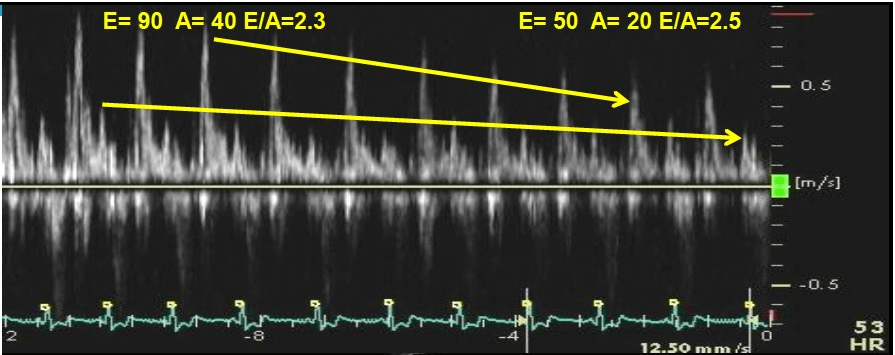

The diastolic function when there is no significant change in E/A with Valsalva maneuver.

What is normal diastolic function?